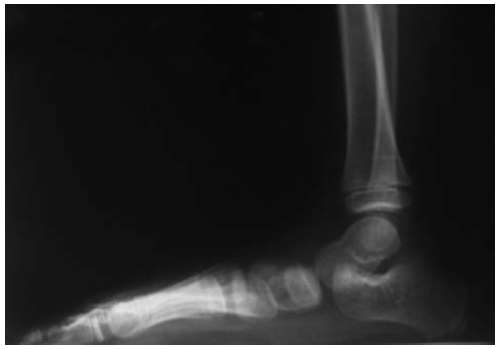

Больная Б., 5 лет, с диагнозом: «ДЦП. Спастическая диплегия. Эквино-плано-вальгусные деформации стоп». Операция — корригирующая остеотомия пяточной кости и пересечение сухожилия икроножной мышцы (рис. 4, 5).

Рис. 4. Рентгенограмма правой стопы в боковой проекции до операции